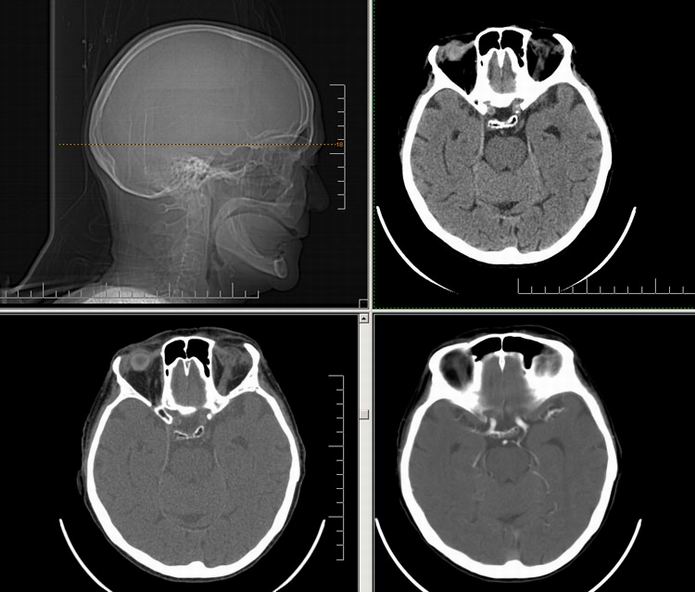

Est ce que qqun a des coupes axiales de crâne pour m'aider à réviser mon anatomie. Merci

Pour compléter tes révisions, Poupette vient de nous faire parvenir ces planches bien utiles: Planches de coupes axiales cérébrales, dans la rubrique COURS / ANATOMIE